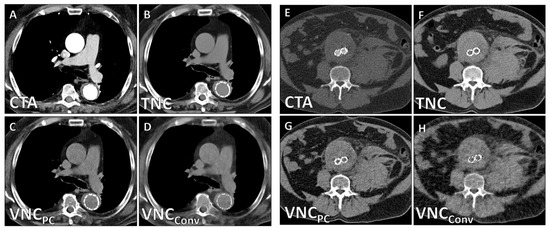

| TNC | VNCPC | VNCConv | Friedman X2 | p | Subgroup Analysis | p | |

|---|---|---|---|---|---|---|---|

| CT values/HU | 44.4 ± 15.5 | 39.1 ± 15.8 | 33.2 ± 15.9 | 19.6 | 0.006 | TNC/VNCPC TNC/VNCConv VNCPC/VNCConv | 0.013 <0.001 <0.001 |

| Noise/HU | 14.9 ± 7.1 | 16.7 ± 7.1 | 18.6 ± 5.3 | 22.8 | 0.003 | TNC/VNCPC TNC/VNCConv VNCPC/VNCConv | <0.001 <0.001 0.021 |

| SNR | 3.3 ± 1.6 | 2.5 ± 1.3 | 1.9 ± 0.9 | 25.0 | <0.001 | TNC/VNCConv TNC/VNCConv VNCPC/VNCConv | <0.001 <0.001 <0.001 |

| Image Quality | 4.2 ± 0.9 | 0.68 (0.44–0.78) | 2.5 ± 0.6 | 0.62 (0.43–0.77) | <0.001 |

| Calcium Subtraction | 4.6 ± 0.5 | 0.75 (0.66–0.82) | 3.0 ± 0.6 | 0.58 (0.40–0.71) | <0.001 |

| Stent Subtraction | 4.7 ± 0.7 | 0.72 (0.58–0.81) | 3.8 ± 1.2 | 0.62 (0.49–0.77) | 0.003 |

| Contrast Subtraction Aorta | 5.0 ± 0.0 | 1.0 (1.0–1.0) | 5.0 ± 0.0 | 1.0 (1.0–1.0) | 1 |

| Contrast Subtraction Total | 4.3 ± 0.8 | 0.86 (0.71–0.95) | 4.0 ± 1.1 | 0.79 (0.66–0.89) | 0.091 |